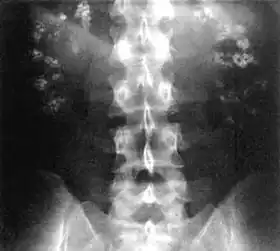

| Significant bilateral nephrocalcinosis (calcification of the kidneys) on a frontal X-ray (radiopacities (white) in the right upper and left upper quadrant of the image), as seen in distal renal tubular acidosis | |